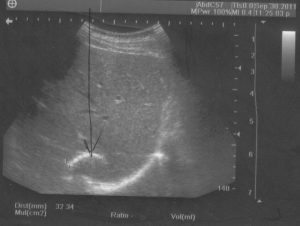

Селезенка — это небольшой орган темно-красного цвета с фиолетовым отливом, который является частью лимфоидной системы. Его форма приплюснутая и продолговатая, напоминающая овал или кофейное зерно. У здорового взрослого человека селезенка имеет мягкую и губчатую структуру. Ее вес составляет около 150-200 грамм, длина — 160 мм, ширина — около 60 мм, толщина — 15-25 мм.

- Спленомегалия, которая является результатом патологического процесса в других органах и приводит к увеличению размеров селезенки.